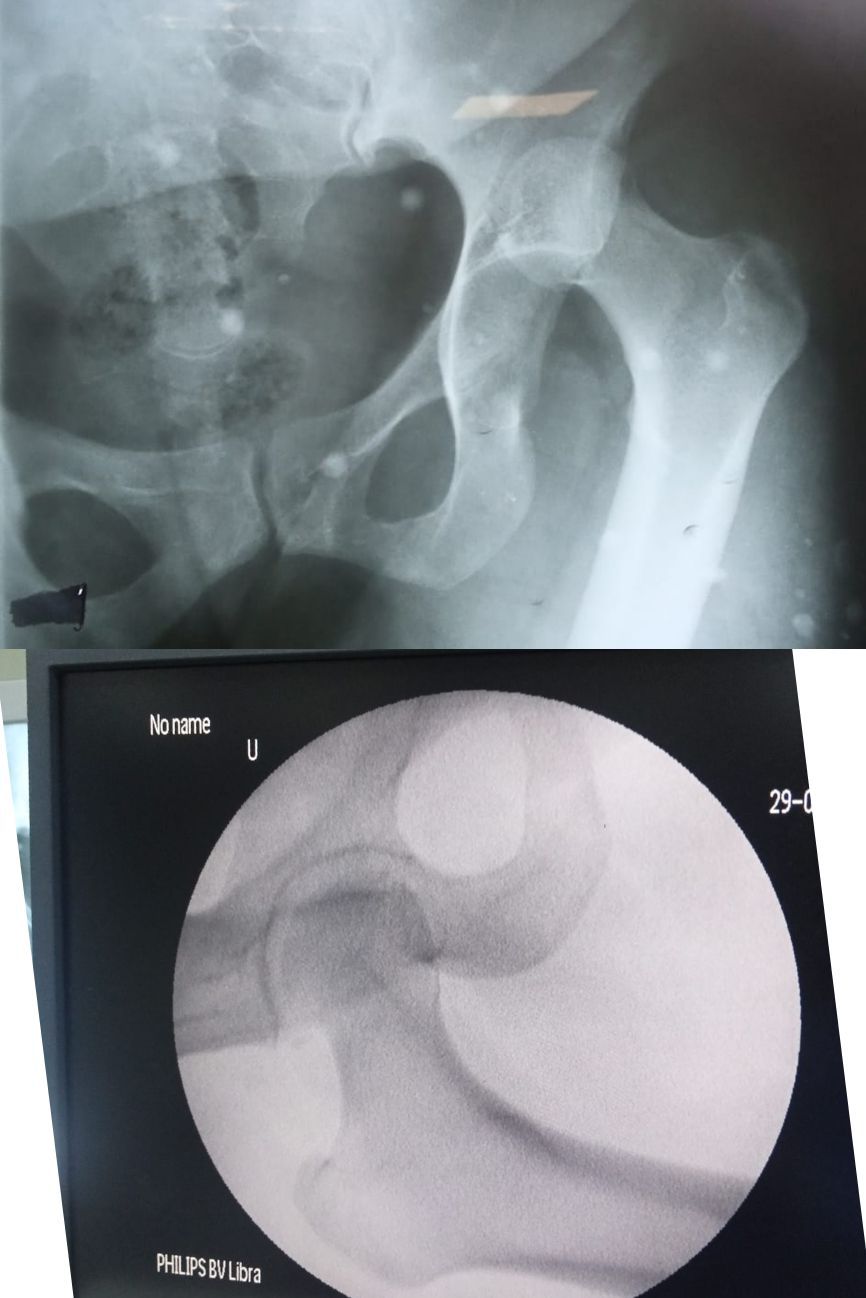

Pic 1-Case of posterior Hip Dx ( Right Hip Joint )

pic 2 urgent Reduction under GA confirm via on table xray